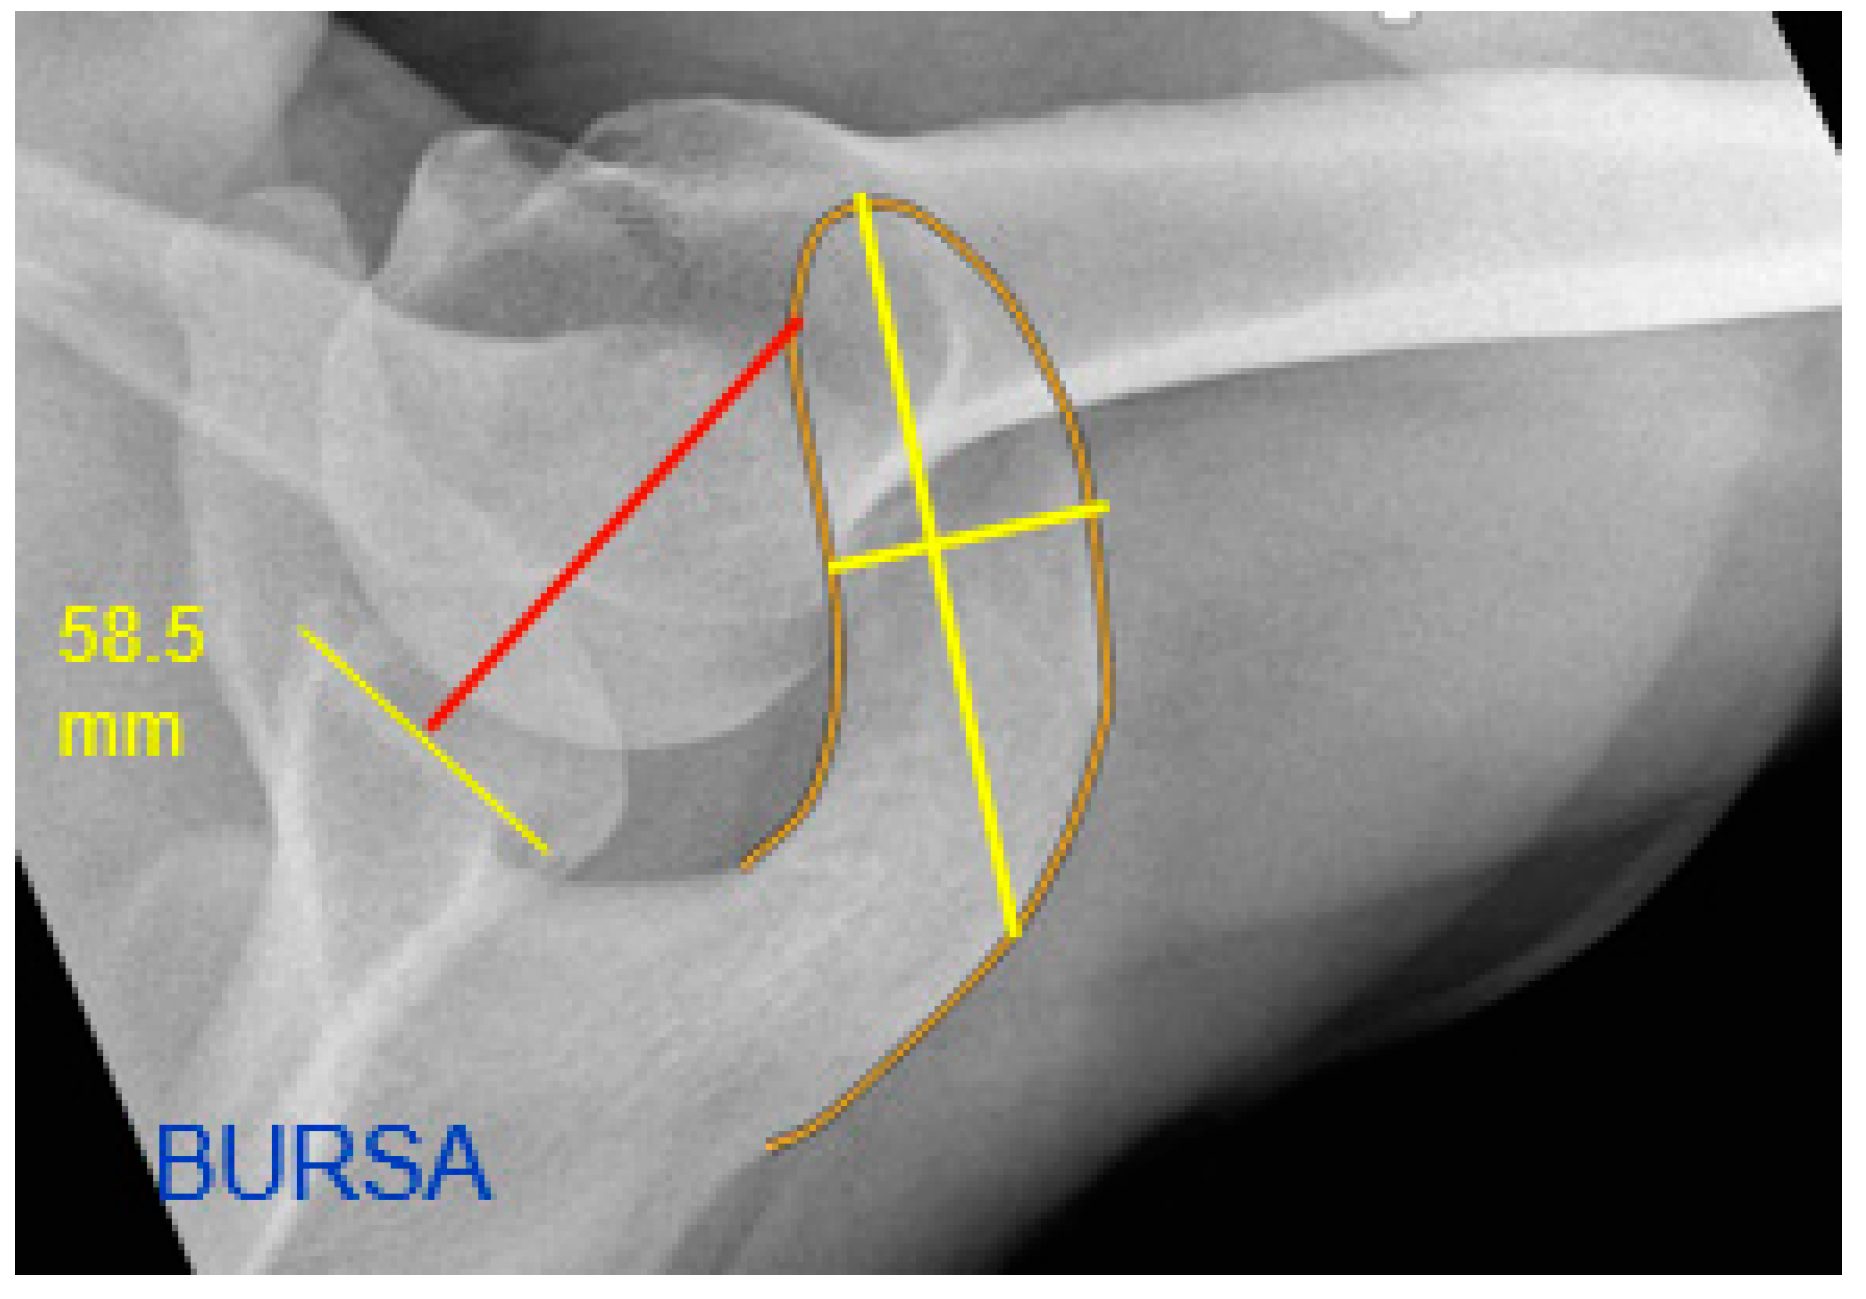

| Medial Acromial Border Offset [mm] | 40.89 (9.20) | 45.16 (8.89) | 0.021 |